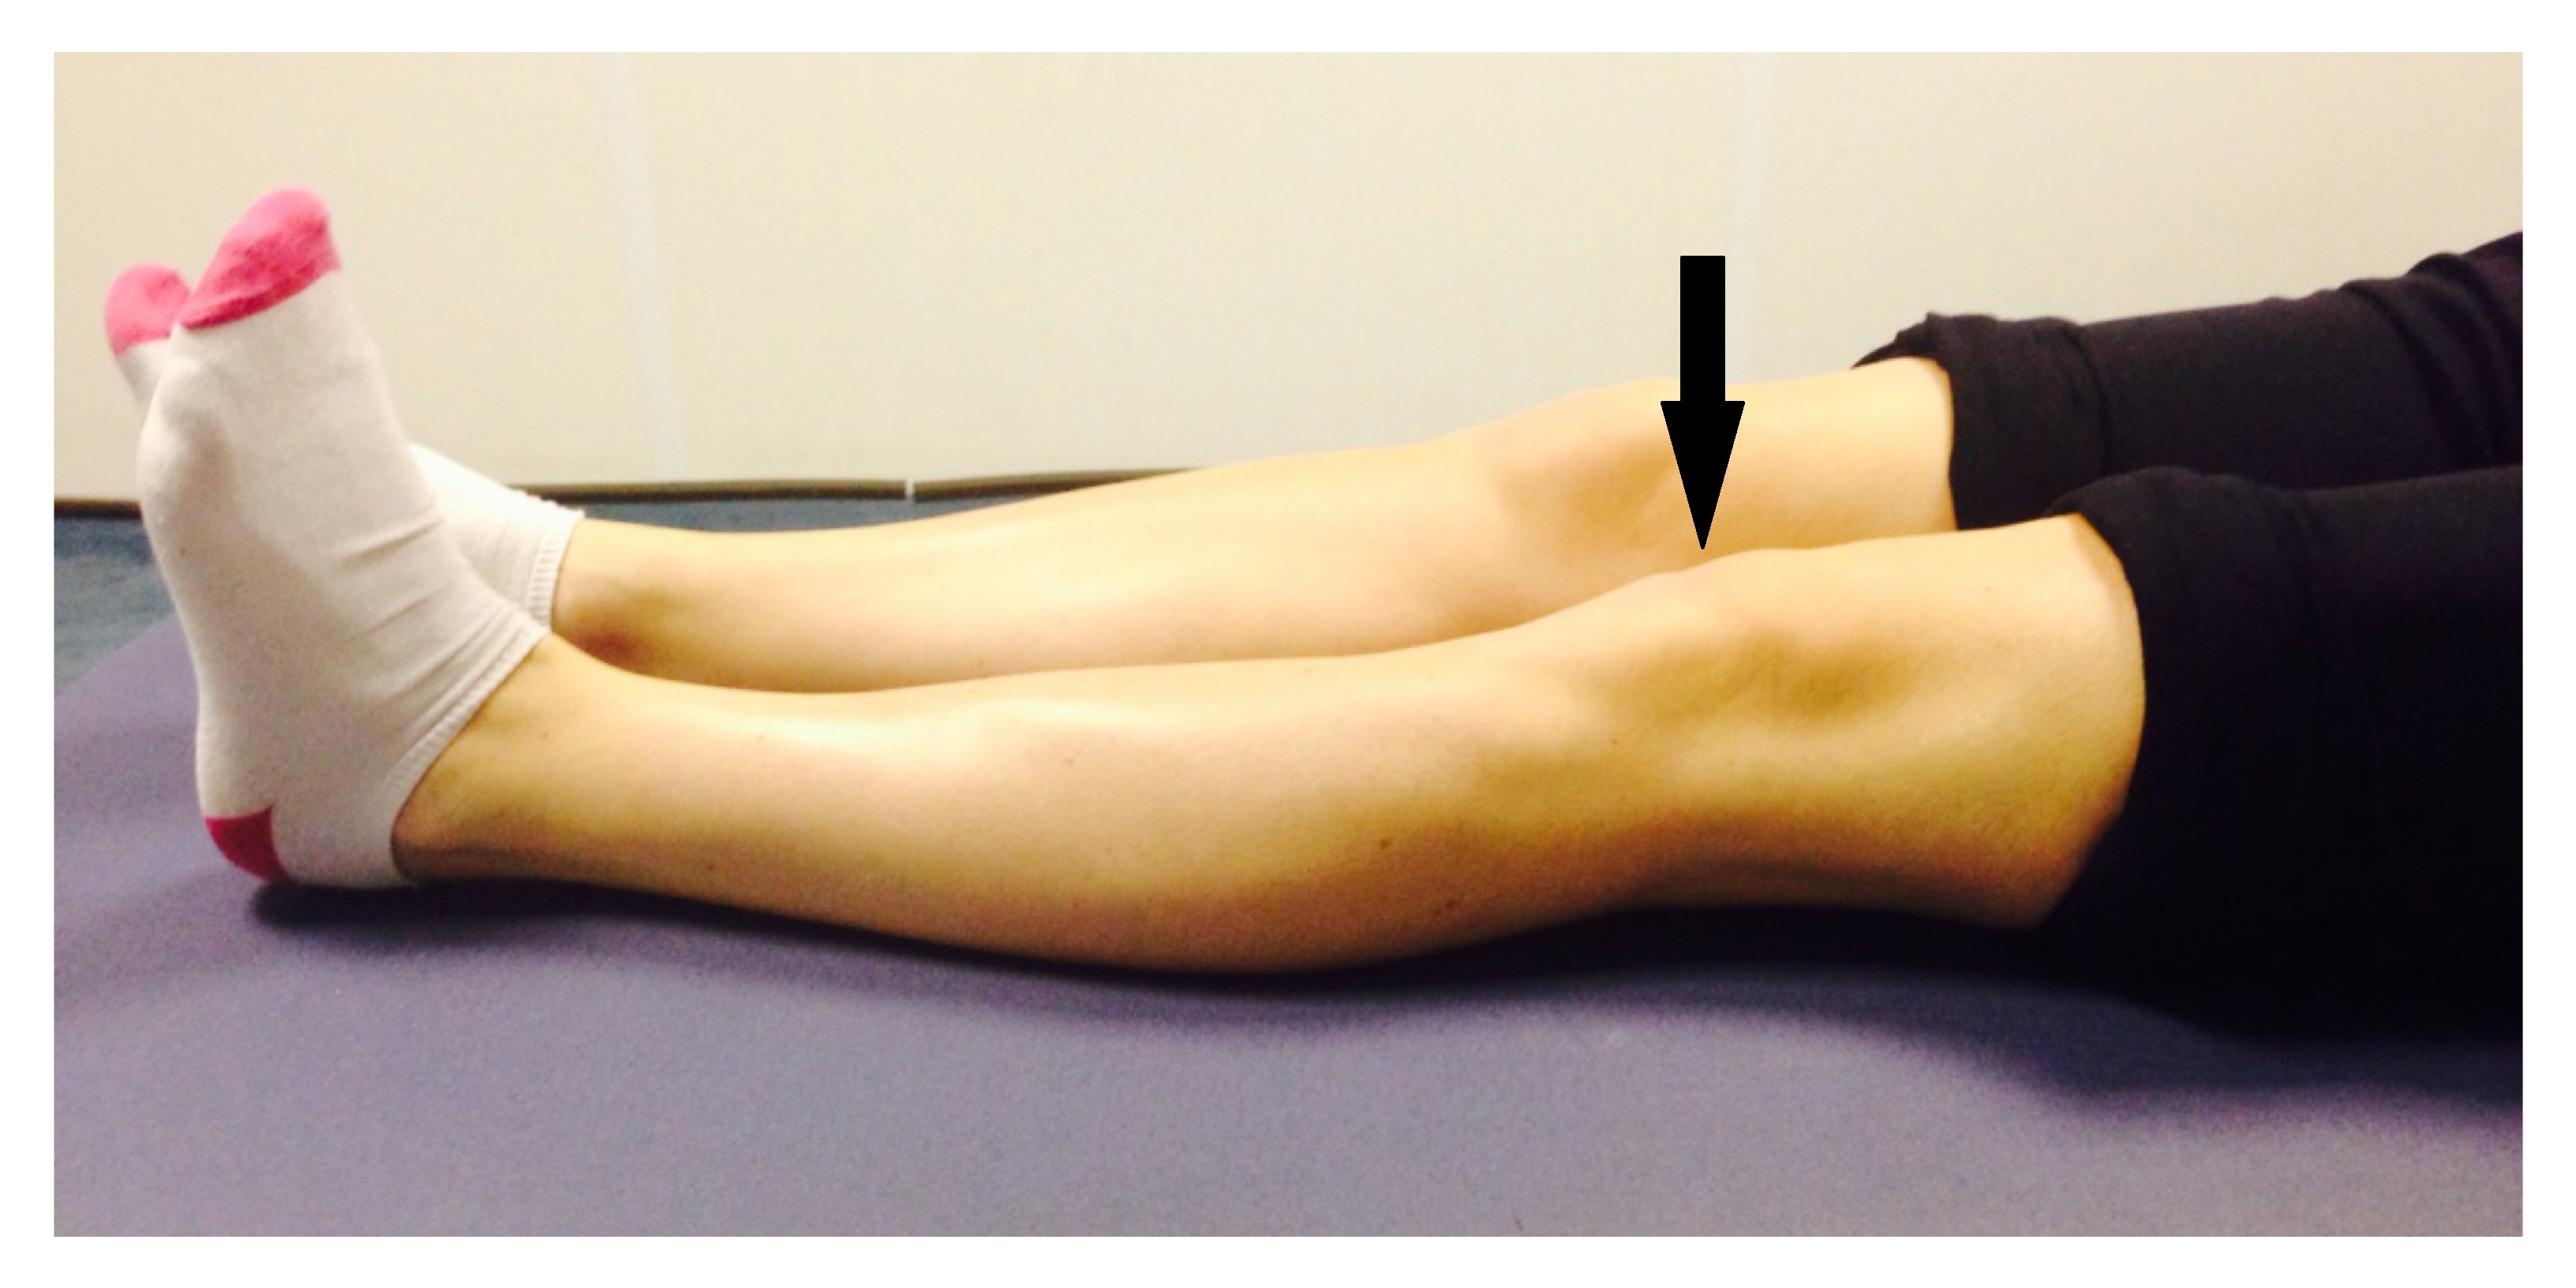

Undisplaced patella fracture Virtual Fracture Clinic